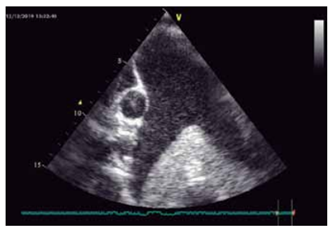

Homem, 60 anos, transplantado cardíaco, vem realizar

ecocardiograma que identifica a seguinte imagem:

(Arquivo pessoal; imagem utilizada com autorização)